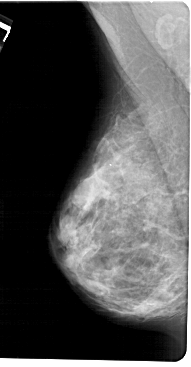

A_1256_1.RIGHT_MLO

RIGHT_MLO LINES 5491 PIXELS_PER_LINE 2566 BITS_PER_PIXEL 12 RESOLUTION 43.5 OVERLAY